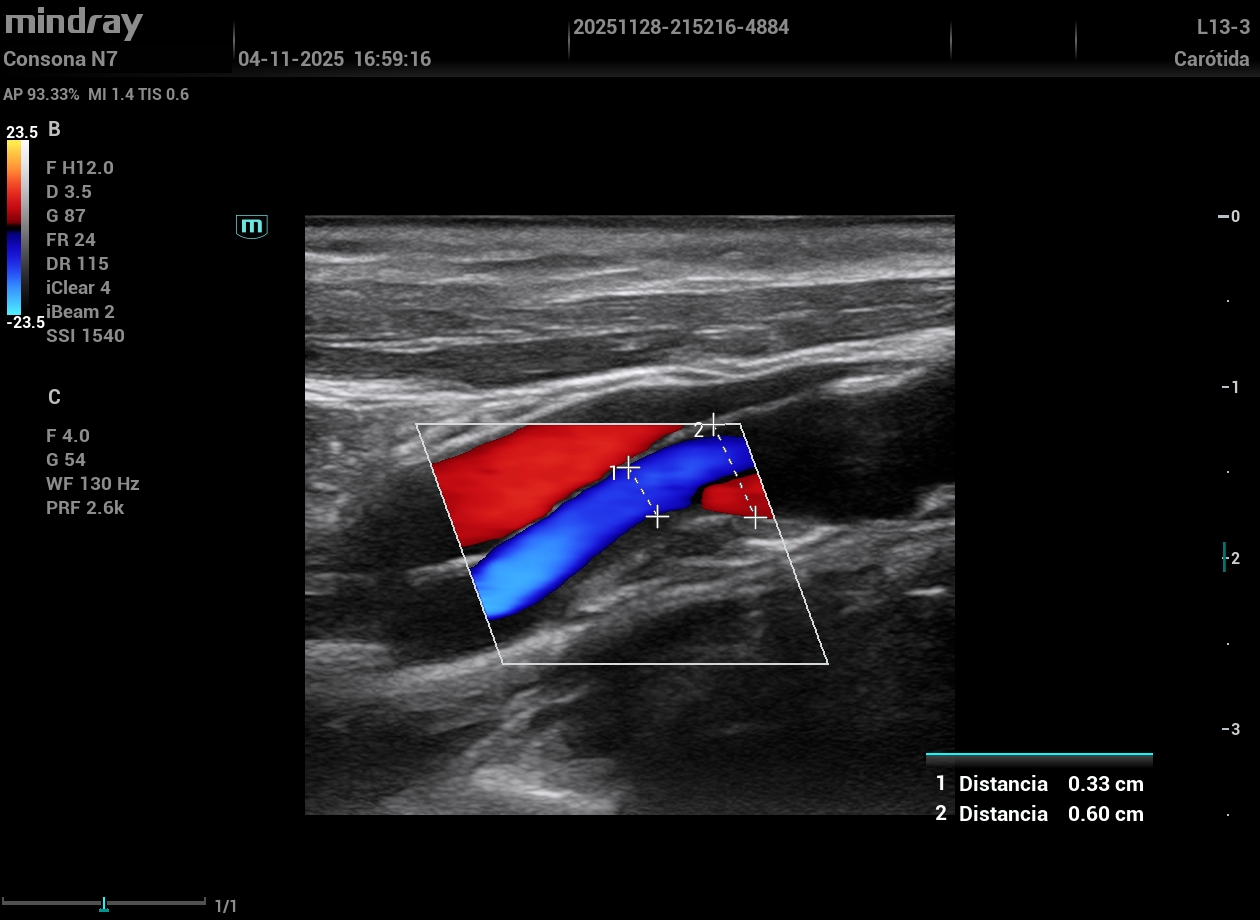

Eco vascular protocolo VASUS +: grandes placas de ateroma tipo 2-3 en ambas carótidas visualizando en carótida interna derecha una obstrucción de más del 50%; ambas femorales con alta carga de placas. ETT: FEVI conservada. HVI concéntrica.

Sospecha de AIT en paciente de alto riesgo cardiovascular.

Ante hallazgos ecográficos, clínica y alto riesgo cardiovascular, impresiona de alta sospecha de AIT frente a sospecha de efectos de Tapentadol. Se ajustan estatinas, se inicia AAS y se realiza e-consulta de caso con NRL para agilizar valoración dado que el paciente está asintomático.